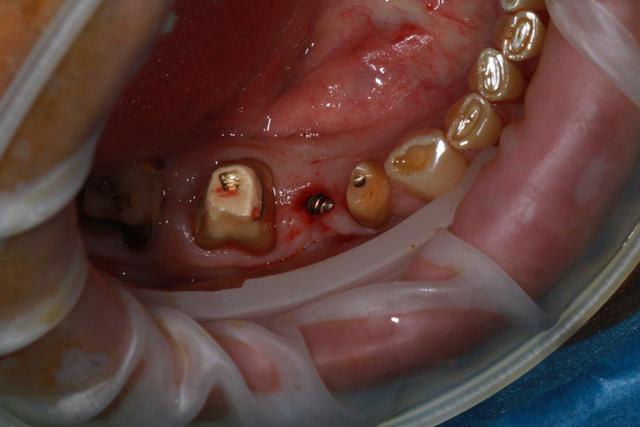

Nouveau patient, pose d'un implant il y a 2 mois....échec sans raisons particulières, douleurs et dépose.

Ce matin repose d'un nouvel implant et comme je ne veux pas prendre de risque, et que les dents adjacentes doivent être couronnées, je pose un bridge en emax press, mais scellé au ciment provisoire...

Si l'implant va bien le bridge sera déposé, coupé, et 44/46 seront collées définitivement après traitement acide et silane.

Si par hasard l'implant pose problème, dépose et bridge collé.

alors là pas du tout, le patient vient me voir pour des implants, donc je fais une étude du cas absence des molaires supérieures, couronnes mandibulaires très ancienne 45 racine cassée, 44 dévitalisée mais passablement déchaussée, donc avulsion de 45 et pose d'un implant avant de refaire les couronnes 46/47 et l'ensemble.

Échec implantaire, et oui ça arrive, même dans un cas paraissant simple.

Dépose gratuite bien sur et repose gratuite aussi, le bridge n'est pas facturé non plus, il le sera sous forme de 2 couronnes que cette fois ci l'implant fonctionne ce que j’espère, ou laissé en bridge si l'implant devait être retiré.

Le fait de scellé au ciment temporaire ne pose en principe pas de problème pour 3 à 6 mois.